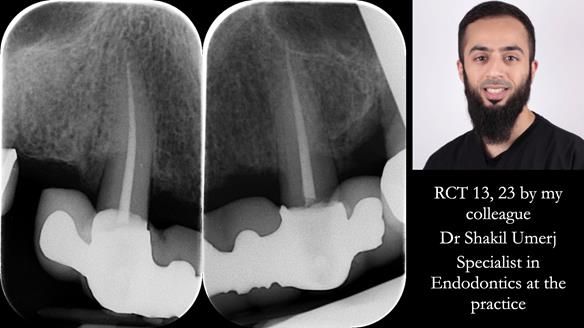

- Retain the upper canines (13 and 23) after root canal treatment, to support a Mk1 immediate complete denture.

Initially, the plan was to retain the canine roots (13 and 23) under the denture after root canal treatment, as set out in the original treatment plan letter.